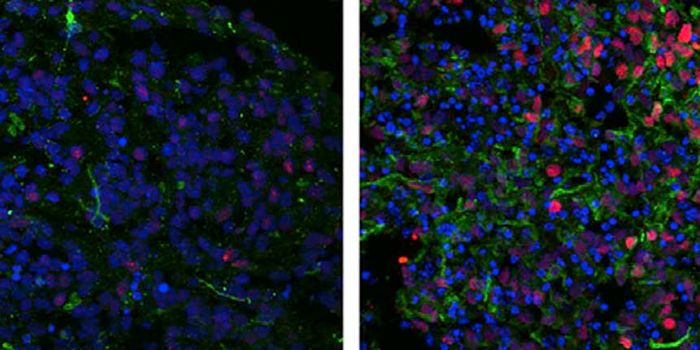

JUL 17, 2015NeuroscienceWhat causes autism? Is there something physical that accounts for behavioral differences?

SEP 19, 2017Cell & Molecular BiologyResearchers have been searching for the cause of autism for many years, and now eight mutations have been found in a sin ...